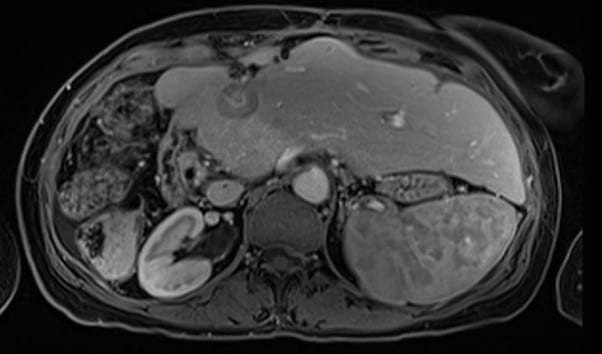

As an illustration, a 64-year-old lady was first diagnosed with breast cancer in 2007, ER/PR negative and HER2 strongly positive. She underwent right mastectomy, FEC/Taxotere chemotherapy, radiotherapy to the right chest wall (40/15) and SCF and trastuzumab. Metastatic disease was first diagnosed in 2010, and over the years she was treated with a variety of systemic therapy agents including vinorelbine, Gemcitabine, Carboplatin, capecitabine and abraxane. Herceptin was continued throughout. In 2012 she underwent right hemihepatectomy for liver metastases, with a further liver resection for recurrent disease in 2013. In 2015 she received Cyberknife SABR to a hilar liver recurrence (field figure 1) 30Gy in 5 fractions – dose limited by adjacent colon, and in 2017 fractionated radiotherapy to the mediastinum for nodal recurrence (55Gy in 20 fractions). She continues to be chemo responsive to taxanes. In 2020 she developed a further 4cm liver metastasis in segment 2/4 (figure 2), for which resection was attempted but failed. She was then referred for further SABR treatment to the liver. There was partial overlap with the previous Cyberknife treatment field.

She was approved for reirradiation by SAT, and treatment on the MR Linac was recommended to minimise any overlap by judicious use of daily GTV and OAR recontouring and adaptation, daily plan reoptimisation and respiratory gated treatment delivery. With these measures we felt an ablative dose could be safely administered despite the previous SABR. The ability to account for interfraction and intrafraction motion on the MRL is especially important for reirradiation. The GTV was defined (figure 3) with a 2mm CTV and 3mm PTV margin and planned for a delivery of 50Gy in 5 fractions. Due to the conformality and steep dose gradient of MRL, 95% of the PTV received 50Gy, with a mean liver dose of just 8.2Gy (figure 4). Liver reirradiation SABR was delivered safely and with minimal toxicity (grade 1 fatigue and nausea). 50% recovery of liver and bowel tolerance was allowed from the previous SABR 5 years ago.

Figure 2 – Diagnostic MRI of “edge recurrence” liver metastasis 2020